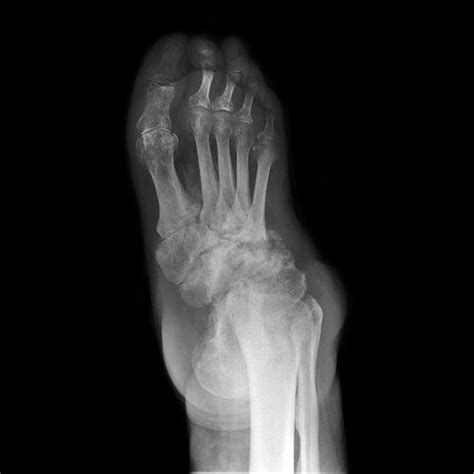

• Neuropathic Arthropathy (Charcot Joint): A progressive degeneration of a weight-bearing joint, usually resulting from nerve damage.

• Medical Imaging: X-rays are standard for assessing bone integrity, while MRI scans are superior for identifying soft tissue or cartilage damage.